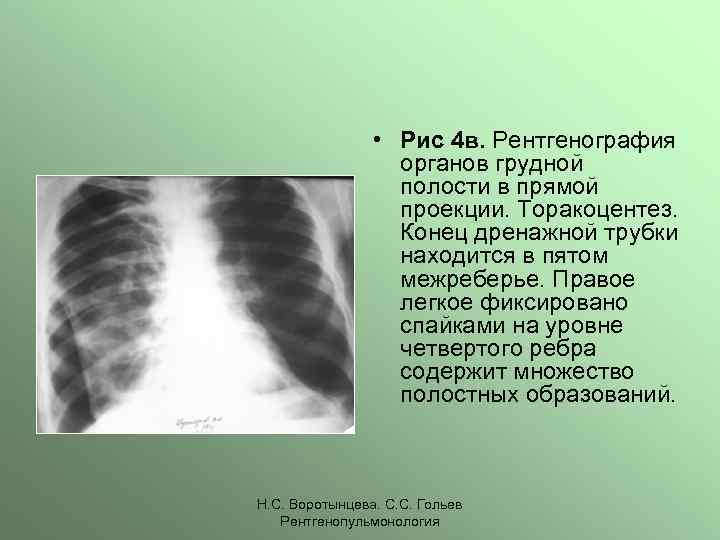

Что такое малоконтрастная рентгенограмма органов грудной клетки